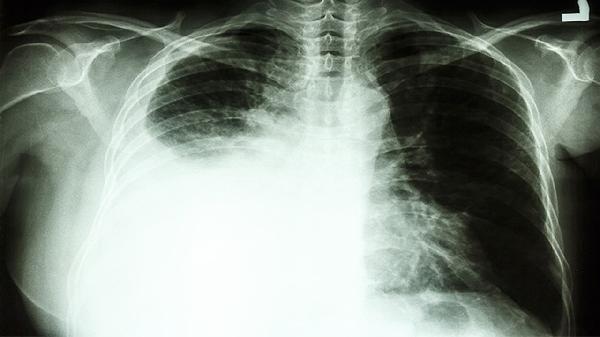

肺癌患者应保持均衡饮食,适当增加优质蛋白和维生素摄入,如鱼肉、鸡蛋、西蓝花等。避免吸烟及接触二手烟,进行适度有氧运动如散步、太极拳。定期复查胸部CT和肿瘤标志物,出现咯血、胸痛加重等情况需立即就医。治疗期间保持良好心态,可通过正念冥想等方式缓解焦虑情绪。